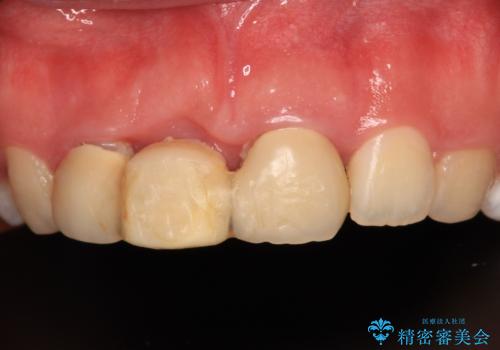

- 矯正治療中に装着していた仮歯を綺麗にしたいとのことで来院された患者様です。

小学生の頃に歯をぶつけて抜歯となりブリッジを装着したそうですが、その後矯正治療を行うに当たりブリッジを切断したとのことでした。

残っている歯根の状態はあまり良くなく、長期的な予後を考えると抜歯を検討するべきでしたが、20代前半という年齢を考え、オールセラミックブリッジにて補綴治療を行うこととしました。